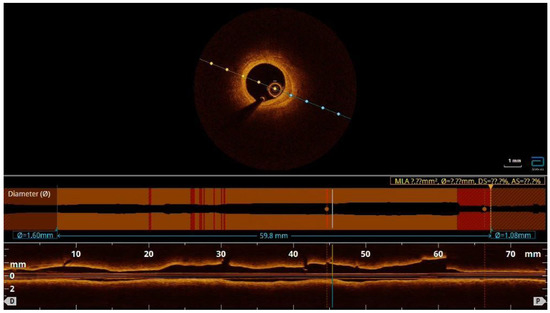

One mount later, the patient felt weak and tired and had atypical symptoms of angina. She had intermittent episodes of supraventricular tachycardia and NYHA II-III heart failure. She was admitted to the hospital and coronary angiography and optical coherent tomography (OCT) were performed. There was one partially absorbed hematoma without compression of the lumen in the LAD medial segment and without signs of persisted dissection (Video S5).